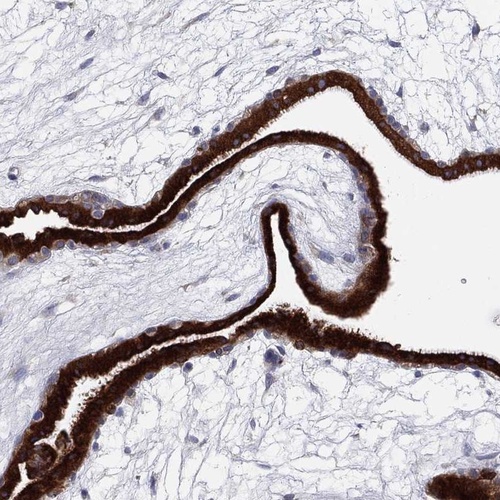

Immunohistochemistry analysis in human placenta and rectum tissues using Anti-TMEM40 antibody. Corresponding TMEM40 RNA-seq data are presented for the same tissues.